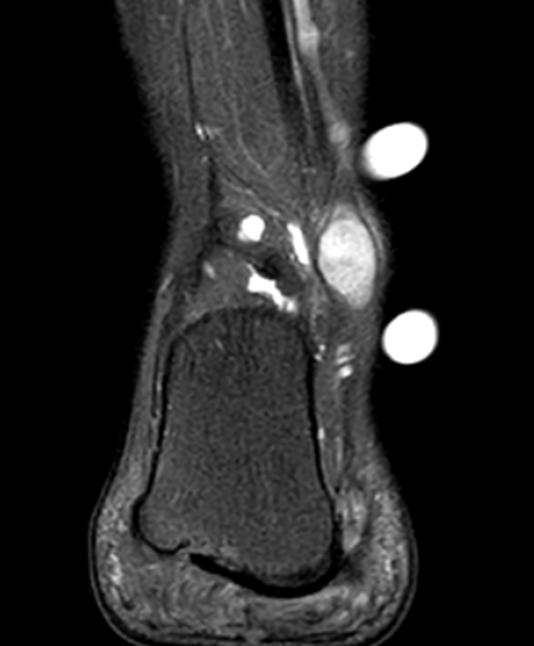

- heterogenous mass on MRI

GCT flexor tendon sheath

GCT of tibialis posterior tendon sheath